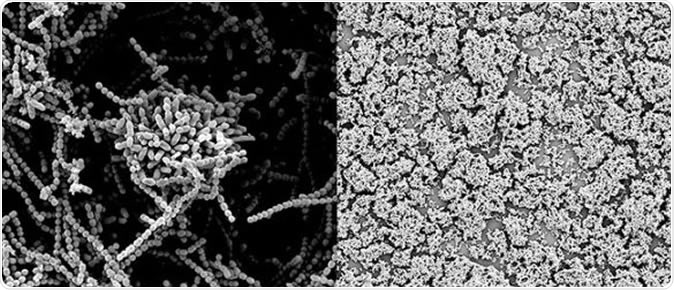

The close-up image on the left illustrates how Strep bacteria normally clump together to form a protective biofilm. The image of the right shows that the biofilm breaks down when a Strep culture is dosed with human milk sugars, exposing more of the bacteria to attack by antibacterial agents. (Steven Townsend / Vanderbilt)

For the study the team collected samples of human milk and isolated the carbohydrate parts of it called oligosaccharides termed human milk oligosaccharides or HMOs. The milk samples came from different donors. These oligosaccharides were then profiled with a mass spectrometry technique to help identify a large number of big biomolecules all at once. Once isolated, these compounds were then added to cultures of Streptococci. The effect of these sugars on the bacteria was studied under the microscope. Results showed that some of these oligosaccharides kill the bacteria directly. They also break down the biofilms or protective coats that the bacteria form around them.